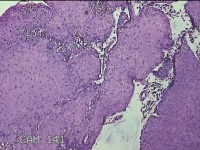

口腔黏膜肿物

性别

男

年龄

6岁

临床诊断

口腔黏膜粘液囊肿

一般病史

右下唇部一月余。

标本名称

大体所见

灰白粉红色囊性肿物0.7x0.5x0.3cm一个,表面光滑。

图1

良性病变。